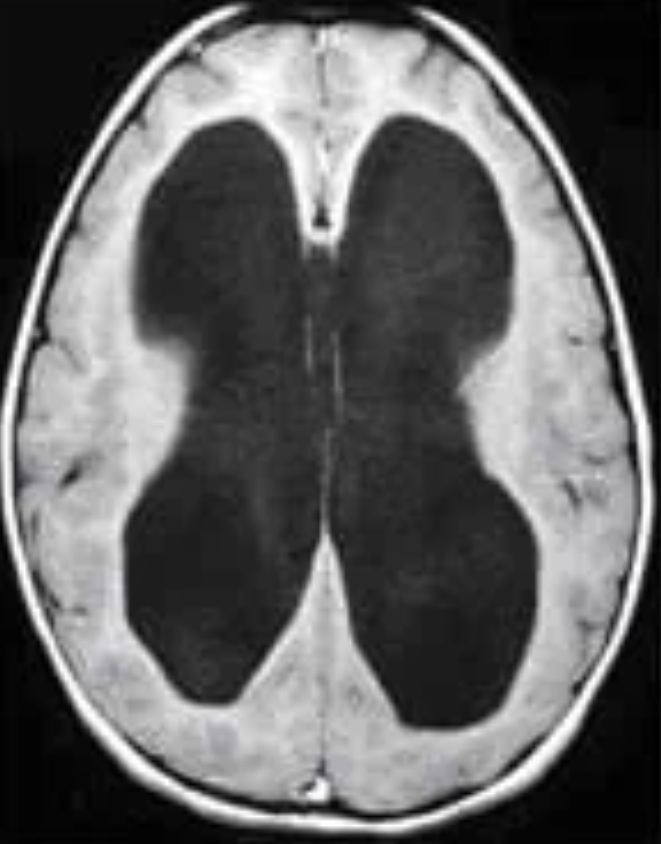

Estudio etiológico, manejo valvular y seguimiento clínico-radiológico a largo plazo.